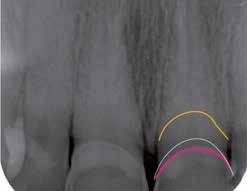

Hölgy páciensem az első konzultáció során tipikus kórtörténetet vázolt fel: Gyermekkora óta szeretett volna fogszabályozó készüléket, hiszen mindig is zavarta a class 2-es eltérésnél tipikusan jellemző nagy overjet (1-3. képek), és természetesen az ezáltal kifelé álló felső metszőfogai, részben a felső metszők protrúziója, részben pedig a disztálisan elhelyezkedő mandibula miatt. Annak ellenére, hogy több fogszabályozó szakorvosnál is járt az évek során, de mivel saggitális eltérése és az alsó metszőfogak torlódása miatt négy kisőrlőfog extrakcióját, illetve emellett sokszor állcsont műtétet is javasoltak neki, nem vágott bele a kezelésbe (4-5. képek).

A fogorvosa – nagyon helyesen – felhívta a figyelmét, hogy parodontális státusza is valószínűsíthetően romlani fog az eltérése miatt, újabb kört futott, immár 39 évesen, de még mindig premoláris fogak húzása és állcsontműtét nélkül szerette volna a fogszabályozást.

A konzultáció során arról is beszéltünk – ahogy az ilyenkor lenni szokott –, sohasem szeretett igazán mosolyogni, de a Pitts Protokolloknak köszönhetően az arc- és mosolyesztétikai céloknak megfelelően kerül megvalósításra az okklúziós korrekció. Az okklúziós kezelési célok az alábbiak voltak: a felső és alsó fogív nivellálása és tágítása, az alsó fogsor/ mandibula mezializálása, valamint a harapás megemelése által a mélyharapás rendezése.

Az esztétikai kezelési céloknál a Pitts elvek szerint a legfontosabb fogak a felső, középső metszők, a cél ezeknek a tökéletes pozícióba állítása. A legfontosabb, hogy a felső, középső metszők labiális felszíne merőleges legyen a Frankfurti Horizontálisra, vagyis természetes fejtartásnál (Natural Head Position) párhuzamos legyen a vertikális síkkal (6. kép) Ehhez az ideális pozícióhoz képest minél protrudáltabbak a felső metszők, annál laposabb, szemből nézve kevésbé ívesebb lesz a mosolyvonal, másrészt optikailag a metszők

hossza is rövidül, azaz a Vertical Incisor Display (Metszőfog láthatóság) csökken. A miniesztétikai, vagyis a mosolyesztétikai eredmény szempontjából egyik jelenség sem kívánatos. A mikroesztétika (a fog- és ínyesztétika) is szorosan hozzátartozik az esztétikai paraméterekhez, ennek tökéletesítése is minden esetben a célok közé tartozik fogkontúrálással vagy esztétikai fogászati felépítéssel, továbbá interproximális redukcióval és szükség esetén lézeres ínykontúrálással (7. kép).

A kezelést Pitts-21-es fogszabályozó készülék alkalmazásával végeztük el. A felső fogíven mosolyvonal beállító esztétikai (Smile Arc Protection - SAP), az alsó fogíven a Spee görbe kiegyenlítését szolgáló funkcionális bracket pozicionálást

alkalmaztunk. Előbbi elengedhetetlen a szép, íves mosolyvonal kialakításához, utóbbi pedig az alsó fogsor mezializálásához, és így az első osztályú sagittális okklúzió kialakításához. Az alsó metszők torlódásának feloldására tolórugókat alkalmaztunk az első hónapban (8. kép)

A protokollok szerves része a mesterséges harapásemelés, melynek segítségével – mintegy kivéve a rágóerők fogmozgatásokat akadályozó hatását – segítjük fogszabályozó rendszer működését. Ezek a ragasztásnál az alsó 7-esekre, majd később a felső 4-esekre kerültek (9. kép).

A harapást beállító elasztikus gumihúzásokat, mint minden kezelésnél, ebben az esetben is folyamatosan, az egész ke-

zelés alatt 24 órában (étkezések kivételével) viselte a páciens. Segítségükkel történt az alsó fogsor mezializálása, és a harapásemelésben is fontos a szerepük a disztálharapás korrekciója során. Az utolsó hónapokban az okklúziós finomítások is részben a segítségükkel történnek az ívhajlítások mellett (10. kép).

A fogkontúrálás és az interproximális redukció alkalmazásával a mikroesztétikai részletek tökéletesítése is megtörtént (11. kép) A kezelés mindössze 16 hónapig tartott, megtörtént a rágófunkció helyreállítása, és az esztétikai végeredmény sokéves várakozás után valóban fordulópontot jelentett páciensünk életében (12-14. képek).